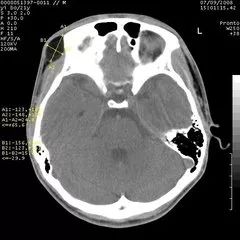

CT与普通体层摄影的区别在哪

从“计算机体层摄影”这个名词可以看出,CT实际上也是一种体层摄影,但它在成像技术上却有了突破性进展。它有了完善的扫描机架,扫描角度极大提高,轻易地实现了横断面的体层摄影。更突出的是,CT首创性地将高性能计算机技术应用到影像领域,又使用高性能的探测器同步检测X线衰减信息,影像精度空前提高,层面结构清晰,完全消除了重叠对病变遮盖的问题。更难能可贵的是,CT能调节“窗宽、窗位”等手段(后续再介绍,也可参阅我写的科普专著),使密度分辨力得到了空前的提高,本来在密度对比方面差别很小的器官策划,也可以在CT上显示出浓淡不同的清晰影像。比如,对于头颅,CT不仅能够看清颅骨的结构,而且能够看到大脑的内部结构如灰质、白质和脑室等。因此,CT极大地拓宽了X线诊断的适用范围。

CT头颅扫描图像